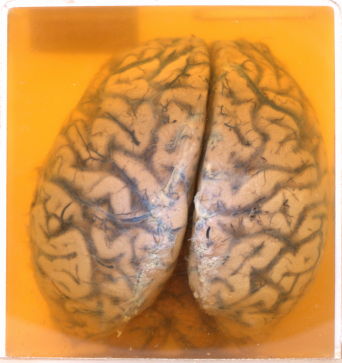

A.2.1 Meningitis

Thick exudates covering the brain surface.

The gyri are flattened & sulci are narrow.

Prominent vasculature over the surface of the brain are seen.